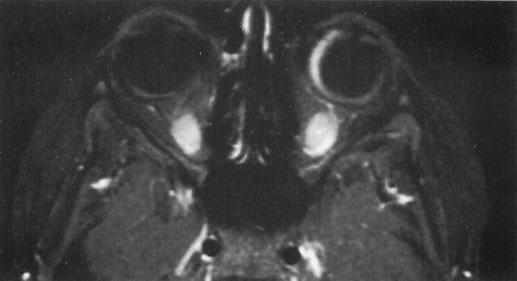

The role of MRI in the evaluation of intraocular masquerade syndromes is unclear. There was initial enthusiasm about the possibility of differentiating atypical uveal melanomas from hemorrhagic-simulating lesions based on the unique paramagnetic properties of melanin.13 In relation to vitreous, a uveal melanoma typically has a bright signal on a T1 image and a dark signal on a T2 image. In contrast, hemorrhagic processes tend to be either bright or dark on a T1 image and bright on a T2 image.14

Unfortunately, there are several problems with MRI for uveal melanoma diagnosis. First, several investigators have shown that unless high field-strength, thin-section scans with surface coils are used, the quality of data obtained is suboptimal.15 Second, even in a state-of-the-art center, we have had a number of cases in which we were unable to differentiate between a uveal melanoma and a simulating lesion on the basis of MRI data. We obtain MRI studies in older patients with opaque media, equivocal ultrasonographic data, and large masses. In some of these cases, the MRI is diagnostic of either a melanoma or an extramacular disciform (hemorrhagic) process. It is also a useful adjunctive study if localized extraocular extension is suspected. In equivocal cases, however, we proceed to using invasive diagnostic techniques, such as fine-needle aspiration biopsy (FNAB) (see Metastatic Tumors).